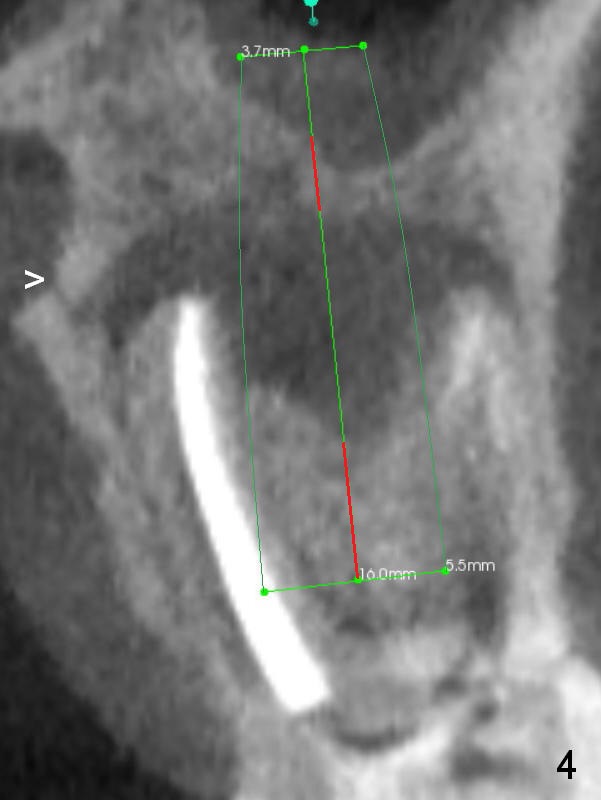

A 34-year-old man has persistent large periradicular radiolucency (Fig.1) after root canal therapy with a fistula (Fig.2). It appears that immediately after extraction (no Antibiotic) a long implant (15 or 16 mm, green outline) should be placed to bypass the bony defect with 2-point fixation (septum and sinus floor; Fig.3 (CBCT sagittal section), 4 (coronal section) red line). A shorter implant, which is placed at the septum (4-5 mm tall), is not expected to be stable. The diameter of the implant is to be determined after sequential osteotomy. The minimal will be 4 mm (Fig.5 axial section) as long as the implant or osteotomy does not perforate the palatal (P) or buccal (B) socket substantially. The bone density at the septum and the sinus floor is 1100 and 200-400 units, respectively. Drills and osteotomes (Tatum or Magic Expanders) will be used for osteotomy in these 2 segments, respectively.